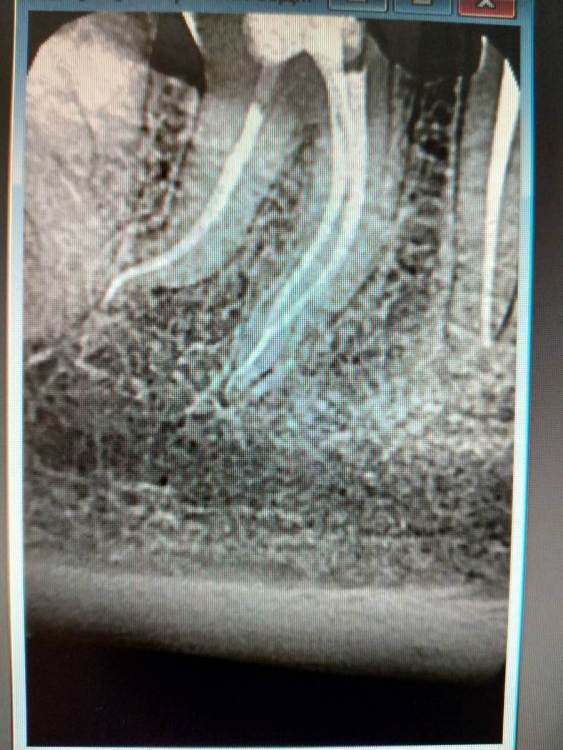

4.7 пульпит.2 визита SX -> S1 короткий -> scout -> Coco+2 плюс патфаилы 1-2 номер, иногда даже в ручном режиме до "0" по аплоку, финиш на 25.02 профайл руками.Гибридная паковка с  эйчем.

1.2.jpg